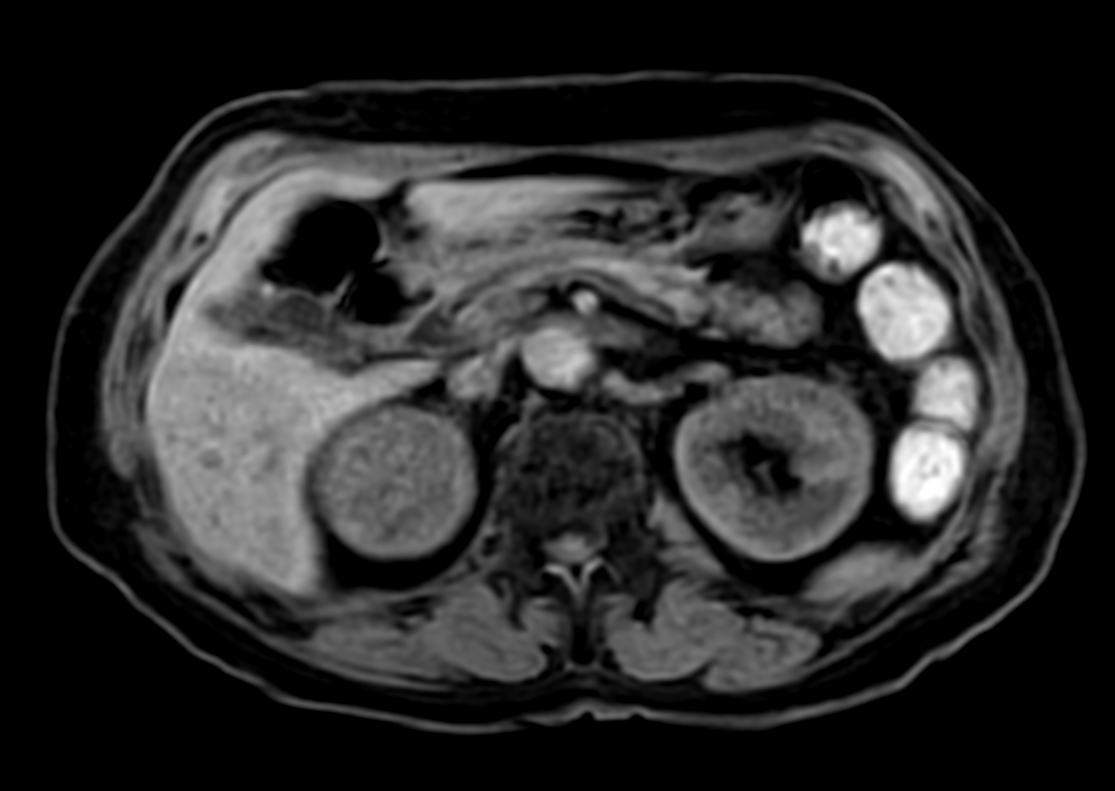

Patient with a kidney lesion. The ExamCard includes techniques for 3D imaging (PelvisVIEW, eTHRIVE) allowing for multiple image directions in one single scan, efficient fat-free imaging over large field-of-views (mDIXON XD), a multi-phase contrast-enhanced sequence (4D FreeBreathing) to improve imaging confidence and Compressed SENSE to accelerate the entire exam.

DWI b800